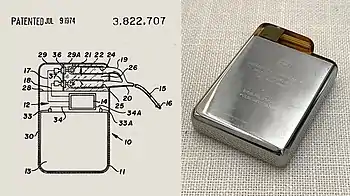

The pacemaker generator is a hermetically sealed device containing a power source, usually a lithium battery, a sensing amplifier which processes the electrical manifestation of naturally occurring heart beats as sensed by the heart electrodes, the computer logic for the pacemaker and the output circuitry which delivers the pacing impulse to the electrodes.

The outer casing of pacemakers is so designed that it will rarely be rejected by the body's immune system. It is usually made of titanium, which is inert in the body.

The preceding implantable devices all suffered from the unreliability and short lifetime of the available primary cell technology, mainly the mercury battery. In the late 1960s, several companies, including ARCO in the US, developed isotope-powered pacemakers, but this development was overtaken by the development in 1971 of the lithium iodide cell by Wilson Greatbatch.[88] Lithium-iodide or lithium anode cells became the standard for pacemaker designs.

A further impediment to the reliability of the early devices was the diffusion of water vapor from body fluids through the epoxy resin encapsulation, affecting the electronic circuitry. This phenomenon was overcome by encasing the pacemaker generator in a hermetically sealed metal case, initially by Telectronics of Australia in 1969, followed by Cardiac Pacemakers, Inc. of St. Paul, Minnesota in 1972. This technology, using titanium as the encasing metal, became the standard by the mid-1970s.

On July 9, 1974, Manuel A. Villafaña and Anthony Adducci, the founders of Cardiac Pacemakers, Inc. (Guidant), manufactured the world's first pacemaker with a lithium anode and a lithium-iodide electrolyte solid-state battery. Lithium-iodide or lithium anode cells increased the life of pacemakers from one year to as long as eleven years, and has become the standard for pacemaker designs. They began designing and testing their implantable cardiac pacemaker powered by a new longer-life lithium battery in 1971. The first patient to receive a CPI pacemaker emerged from surgery in June 1973.[87][89]